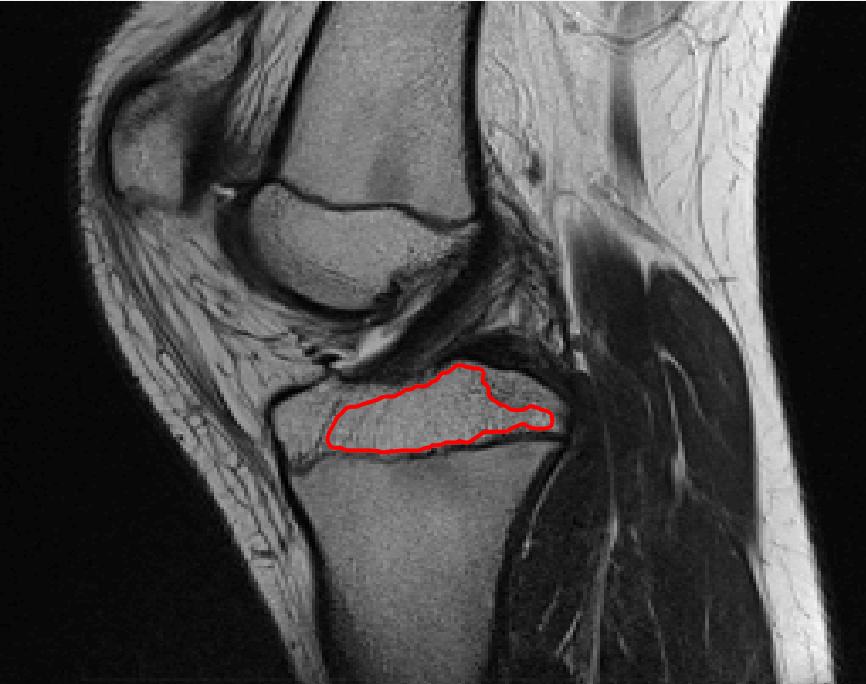

Four sets of test results are shown below. In Test 1 we compare models M1 – M6 to the proposed model M7 for two images which are hard to segment. The first is a CT scan from which we would like to segment the lower portion of the heart, the second is an MRI scan of a knee and we would like to segment the top of the Tibia. See Figure 9 for the test images and the marker sets used in the experiments. In Test 2 we will review the sensitivity of the proposed model to the main parameters. In Test 3 we will give several results achieved by the model using marker and anti-marker sets. In Test 4 we show the initialisation independence and marker independence of the Geodesic Model on real images.

In this test we give the segmentation results for models M1 – M7 for the two challenging test images shown in Figure 9. The marker and anti-marker sets used in the experiments are also shown in this figure. After extensive parameter tuning, the best final segmentation results for each of the models are shown in Figures 10 and 11. For M1 – M4 we obtain incorrect segmentations in both cases. In particular, the results of M2 and M4 are interesting as the former gives poor results for both images, and the latter gives a reasonable result for Test Image 1 and a poor result for Test Image 2. In the case of M2, the regularisation term includes the edge detector and the distance penalty term (see (4)). It is precisely this which permits the poor result in Figures 10(b) and 11(b) as the edge detector is zero along the contour and the fitting terms are satisfied there (both intensity and area constraints) – the distance term is not large enough to counteract the effect of these. In the case of M4, the distance term and edge detector are separated from the regulariser and are used to weight the Chan-Vese fitting terms (see (9)). The poor segmentation in Figure 11(b) is due to the Chan-Vese terms encouraging segmentation of bright objects (in this case), weighting enforces these terms at all edges in the image and near . In experiments, we find that M4 performs well when the object to segment is of approximately the highest or lowest intensity in the image, however when this is not the case, results tend to be poor. We see that, in both cases, models M5 and M6 give much improved results to M2 and M4 (obtained by incorporating the geodesic distance penalty into each). The proposed Geodesic Model M7 gives an accurate segmentation in both cases. It remains to compare M5, M6 and M7. We see that M5 is a non-convex model (and cannot be made convex [39]), therefore results are initialisation dependent. It also requires one more parameter than M6 and M7, and an accurate set to give a reasonable area constraint in (4). These limitations lead us to conclude M6 and M7 are better choices than M5. In the case of M6, it has the same number of parameters as M7 and gives good results. M6 can be viewed as the model M7 with weighted intensity fitting terms (compare (18) and (30)). Experimentally, we find that the same quality of segmentation result can be achieved with both models generally, however M6 is more parameter sensitive than M7. This can be seen in the parameter map in Figure 12 with M7 giving an accurate result for a wider range of parameters than M6. To show the improvement of M7 over previous models, we also give an image in Figure 13 which can be accurately segmented with M7 but the correct result is never achieved with M6 (or M3). Therefore we find that M7 outperforms all other models tested M1 – M6.

Test 2 – Test of M7’s sensitivity to changes in its main parameters. In this test we demonstrate that the proposed Geodesic Model is robust to changes in the main parameters. The main parameters in (20) are and . In all tests we set , which is simply a rescaling of the other parameters, and we set . In the first example, in Figure 12, we compare the TC value for various and values for segmentation of a bone in a knee scan. We see that the segmentation is very good for a larger range of and values. For the second example, in Figure 13, we show an image and marker set for which the Spencer-Chen model (M3) and modified Liu et al. model M6 cannot achieve the desired segmentation for any parameter range, but which can be attained for the Geodesic Model for a vast range of parameters. The final example, in Table 1, compares the TC values for various values with fixed parameters and . We use the images and ground truth as shown in Figures 12 and 13: on the synthetic circles image we obtain a perfect segmentation for all values of tested, and in the case of the knee segmentation the results are almost identical for any , above which the quality slowly deteriorates.

Test 3 – Further Results from the Geodesic Model M7. In this test we give some medical segmentation results obtained using the Geodesic Model M7. The results are shown in Figure 14. In the final two columns we use anti-markers to demonstrate how to overcome blurred edges and low contrast edges in an image. These are challenging and it is pleasing to see the correctly segmented results.